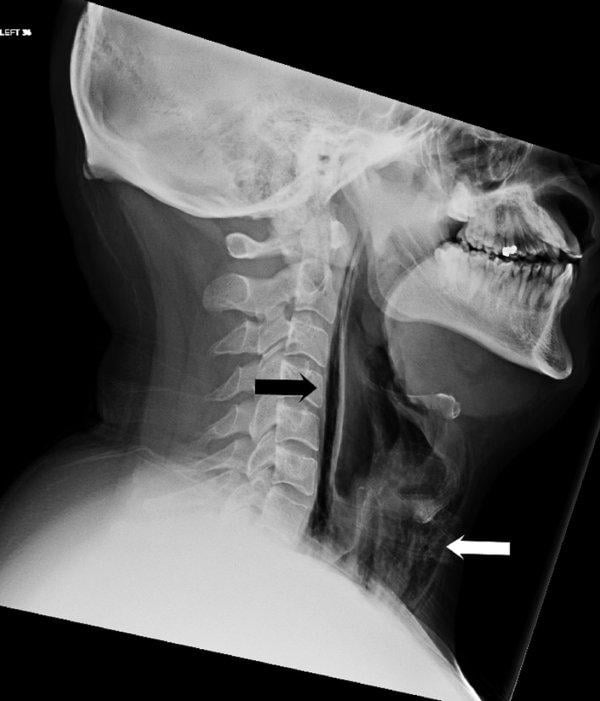

Röntgen sonuçlarında soluk borusunun hasar gördüğünü ve buradan sızan havanın yumuşak dokulara zarar verdiğini belirten talihsiz İngiliz, 7 gün boyunca hastanede yatarak tedavi gördüğünü, tedavi sürecinde de bir hafta boyunca tüp aracılığıyla beslendiğini belirtti.